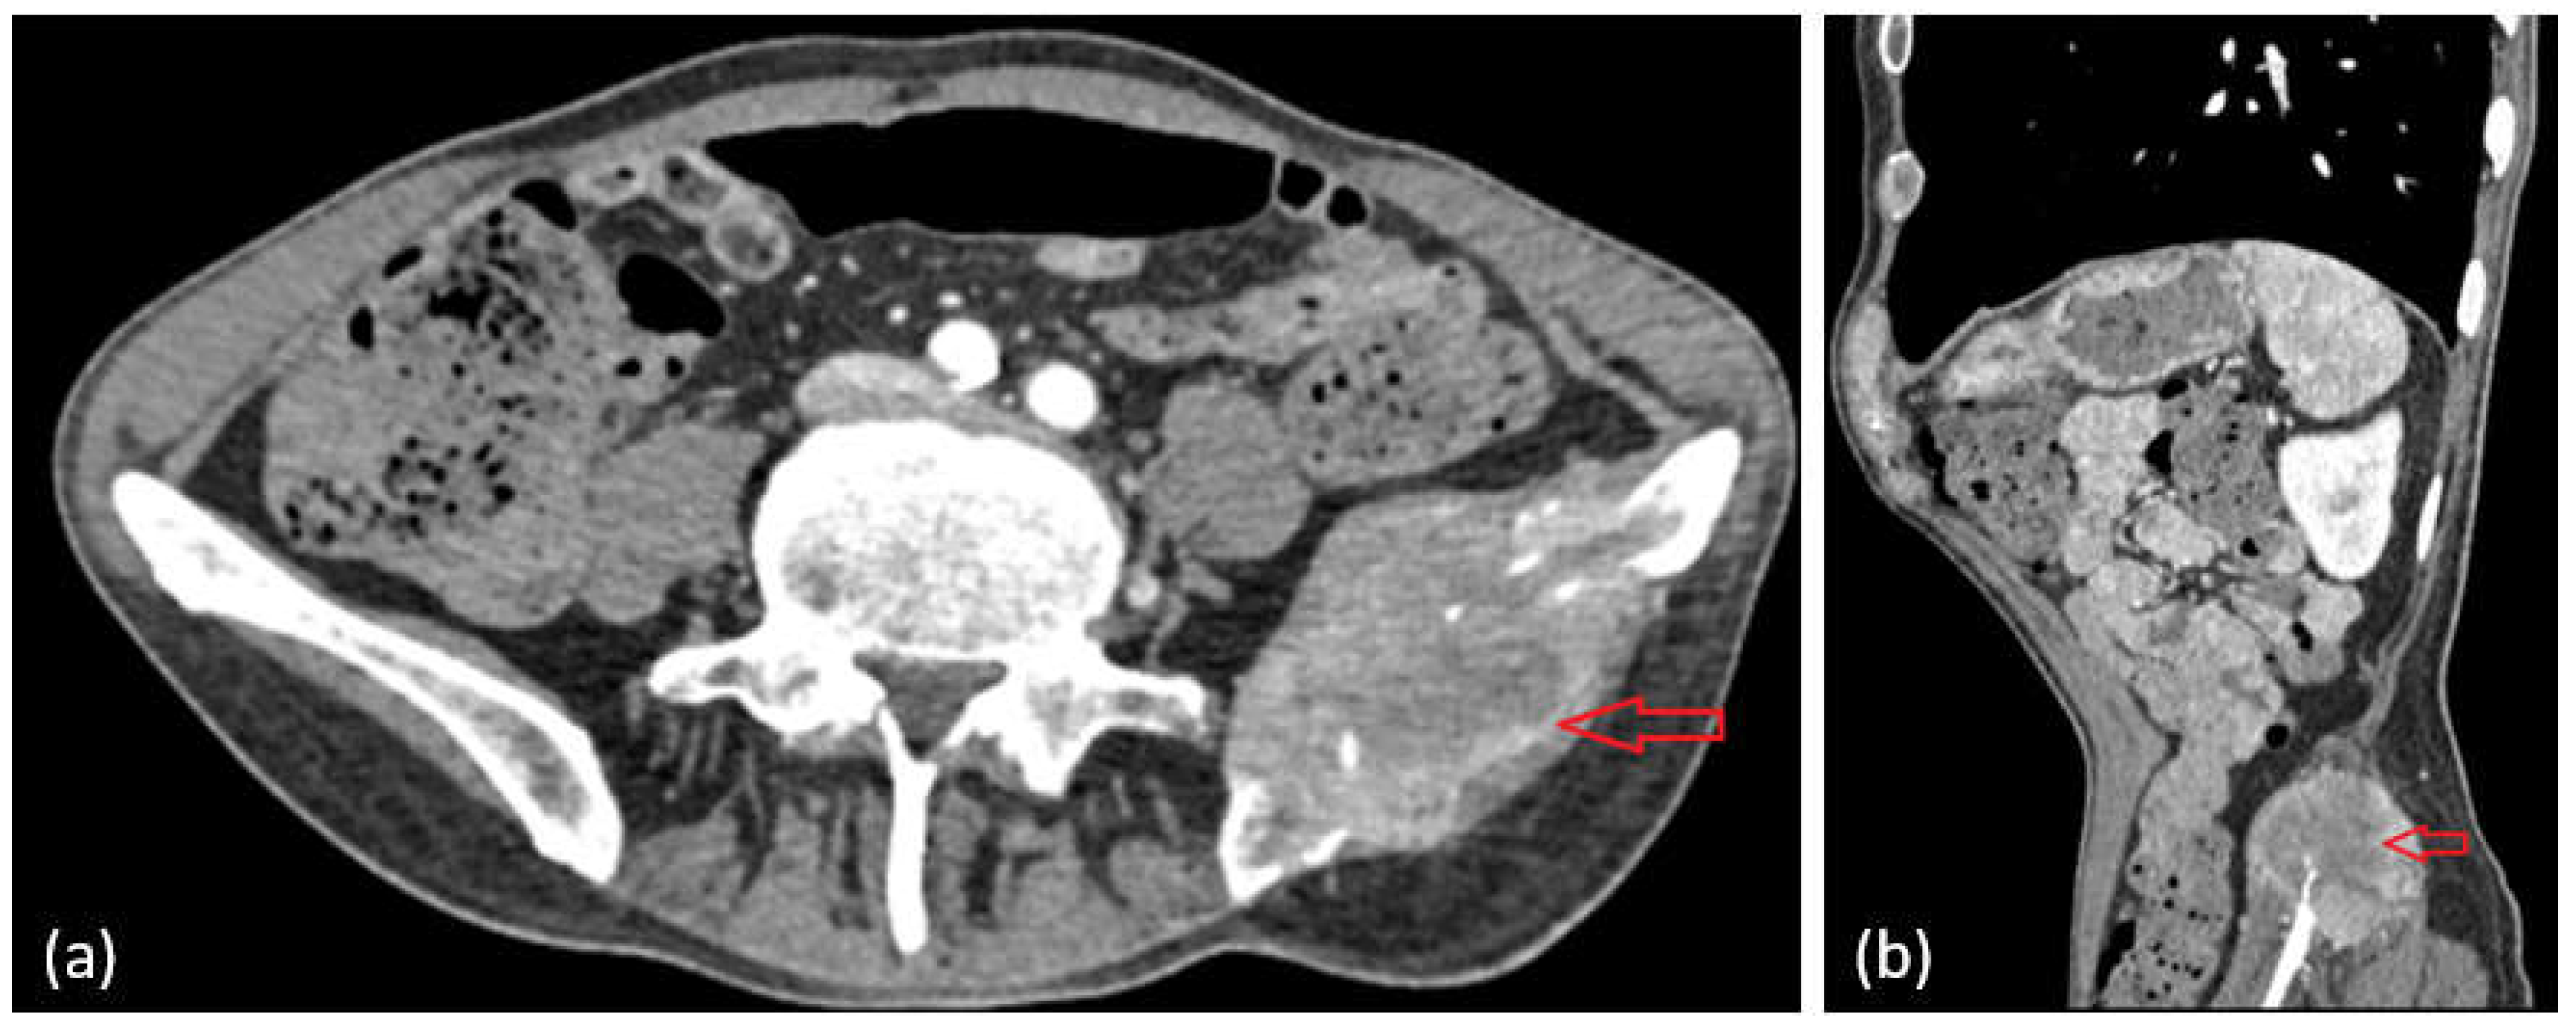

The oncological imaging workup required a contrast-enhanced CT scan of the abdomen and pelvis, which revealed a tumor formation of heterogeneous density, with irregular iodine uptake and poorly defined borders, characterized by invasive lytic behavior involving the left iliac bone and adjacent soft tissues, including the iliac and gluteus medius muscles (Figure 7a,b—red arrow).

Shortly thereafter, the patient’s condition deteriorated, with an onset of severe pain in the right hip, radiating to the posterior side of the left lower limb and with partial relief by the administered analgesic treatment. Given the presence of pleural and pulmonary imaging abnormalities, the tumoral lesion identified in the left iliac region—characterized by its invasive, lytic appearance and the involvement of adjacent soft tissues—is highly suggestive of a secondary (metastatic) process. Nonetheless, histopathological confirmation through biopsy and immunohistochemical analysis is necessary to determine the exact nature of the lesion. We note that, at the moment of this writing, we do not have a biopsy of this iliac lesion.

Figure 7. Secondary osseous involvement of the left iliac bone, exhibiting irregular features and extending into the iliacus and gluteus medius muscles (a,b).